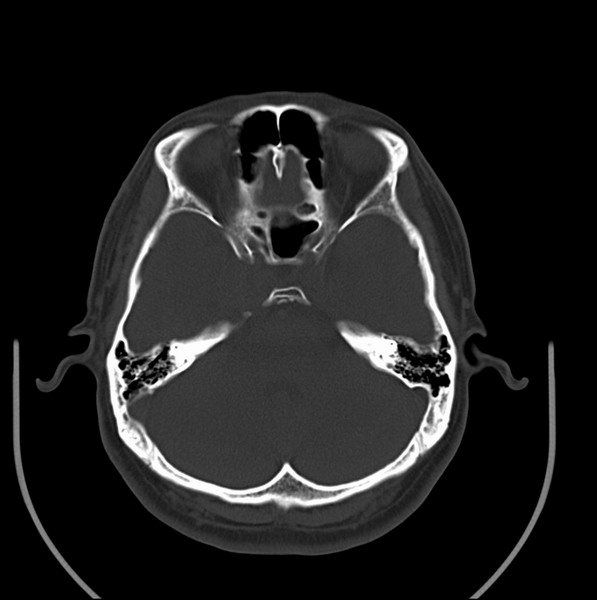

男、30、发现鼻咽部肿瘤侵犯海绵窦,未发现明显淋巴肿。请问国内那家医院治疗鼻咽部肿瘤最好?手术以何种方式为主?病灶可否全部切除?急切期待的大家的帮助。

扫描示鼻咽腔不对称,中度狭窄,右侧咽隐窝消失,局部软组织肿块,鼻咽右侧壁增厚形成肿块,突入鼻咽腔,肿块平扫呈等密度,肿块向深部侵润,右侧翼内外肌受侵,右侧咽旁间隙变窄;向后生长,头长肌界线欠清,向后上生长侵犯同侧颈动脉鞘区。双侧海绵窦增宽,内见软组织影与鼻咽部肿块相连。考虑鼻咽癌。鼻咽癌主要是放射治疗,且效果较好;到当地有治疗设备较大医院治疗即可。

这个病例有点特殊,和常见的鼻咽癌不太一样,以向颅内侵犯为主,骨质破坏区小。鼻咽癌首先要考虑,有没有其他可能?本人不会看mr片,期待有人能讲解,期待病理。

鼻咽部新生物(纤维血管瘤?鼻咽癌?)侵犯右侧中颅窝底及右侧海绵窦;建议必要时活检定性。

鼻咽部新生物侵犯右侧中颅窝底及右侧海绵窦,鼻咽癌可能性大。建议增强扫描。纤维血管瘤禁忌穿刺。

典型鼻咽癌侵犯右侧海绵窦(对放疗敏感)